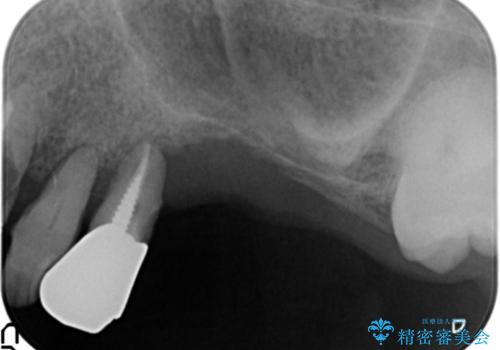

精査したところ、歯周病に罹患した歯を長年放置したことから骨吸収が進行し、上顎骨の厚みはとても薄くなっていました。

全顎的な歯周病治療を行ったのち、上顎洞底挙上術(上顎骨に骨を増やす手術)を併用したインプラント埋入を行いました。

インプラントの種類:ストローマン BLT